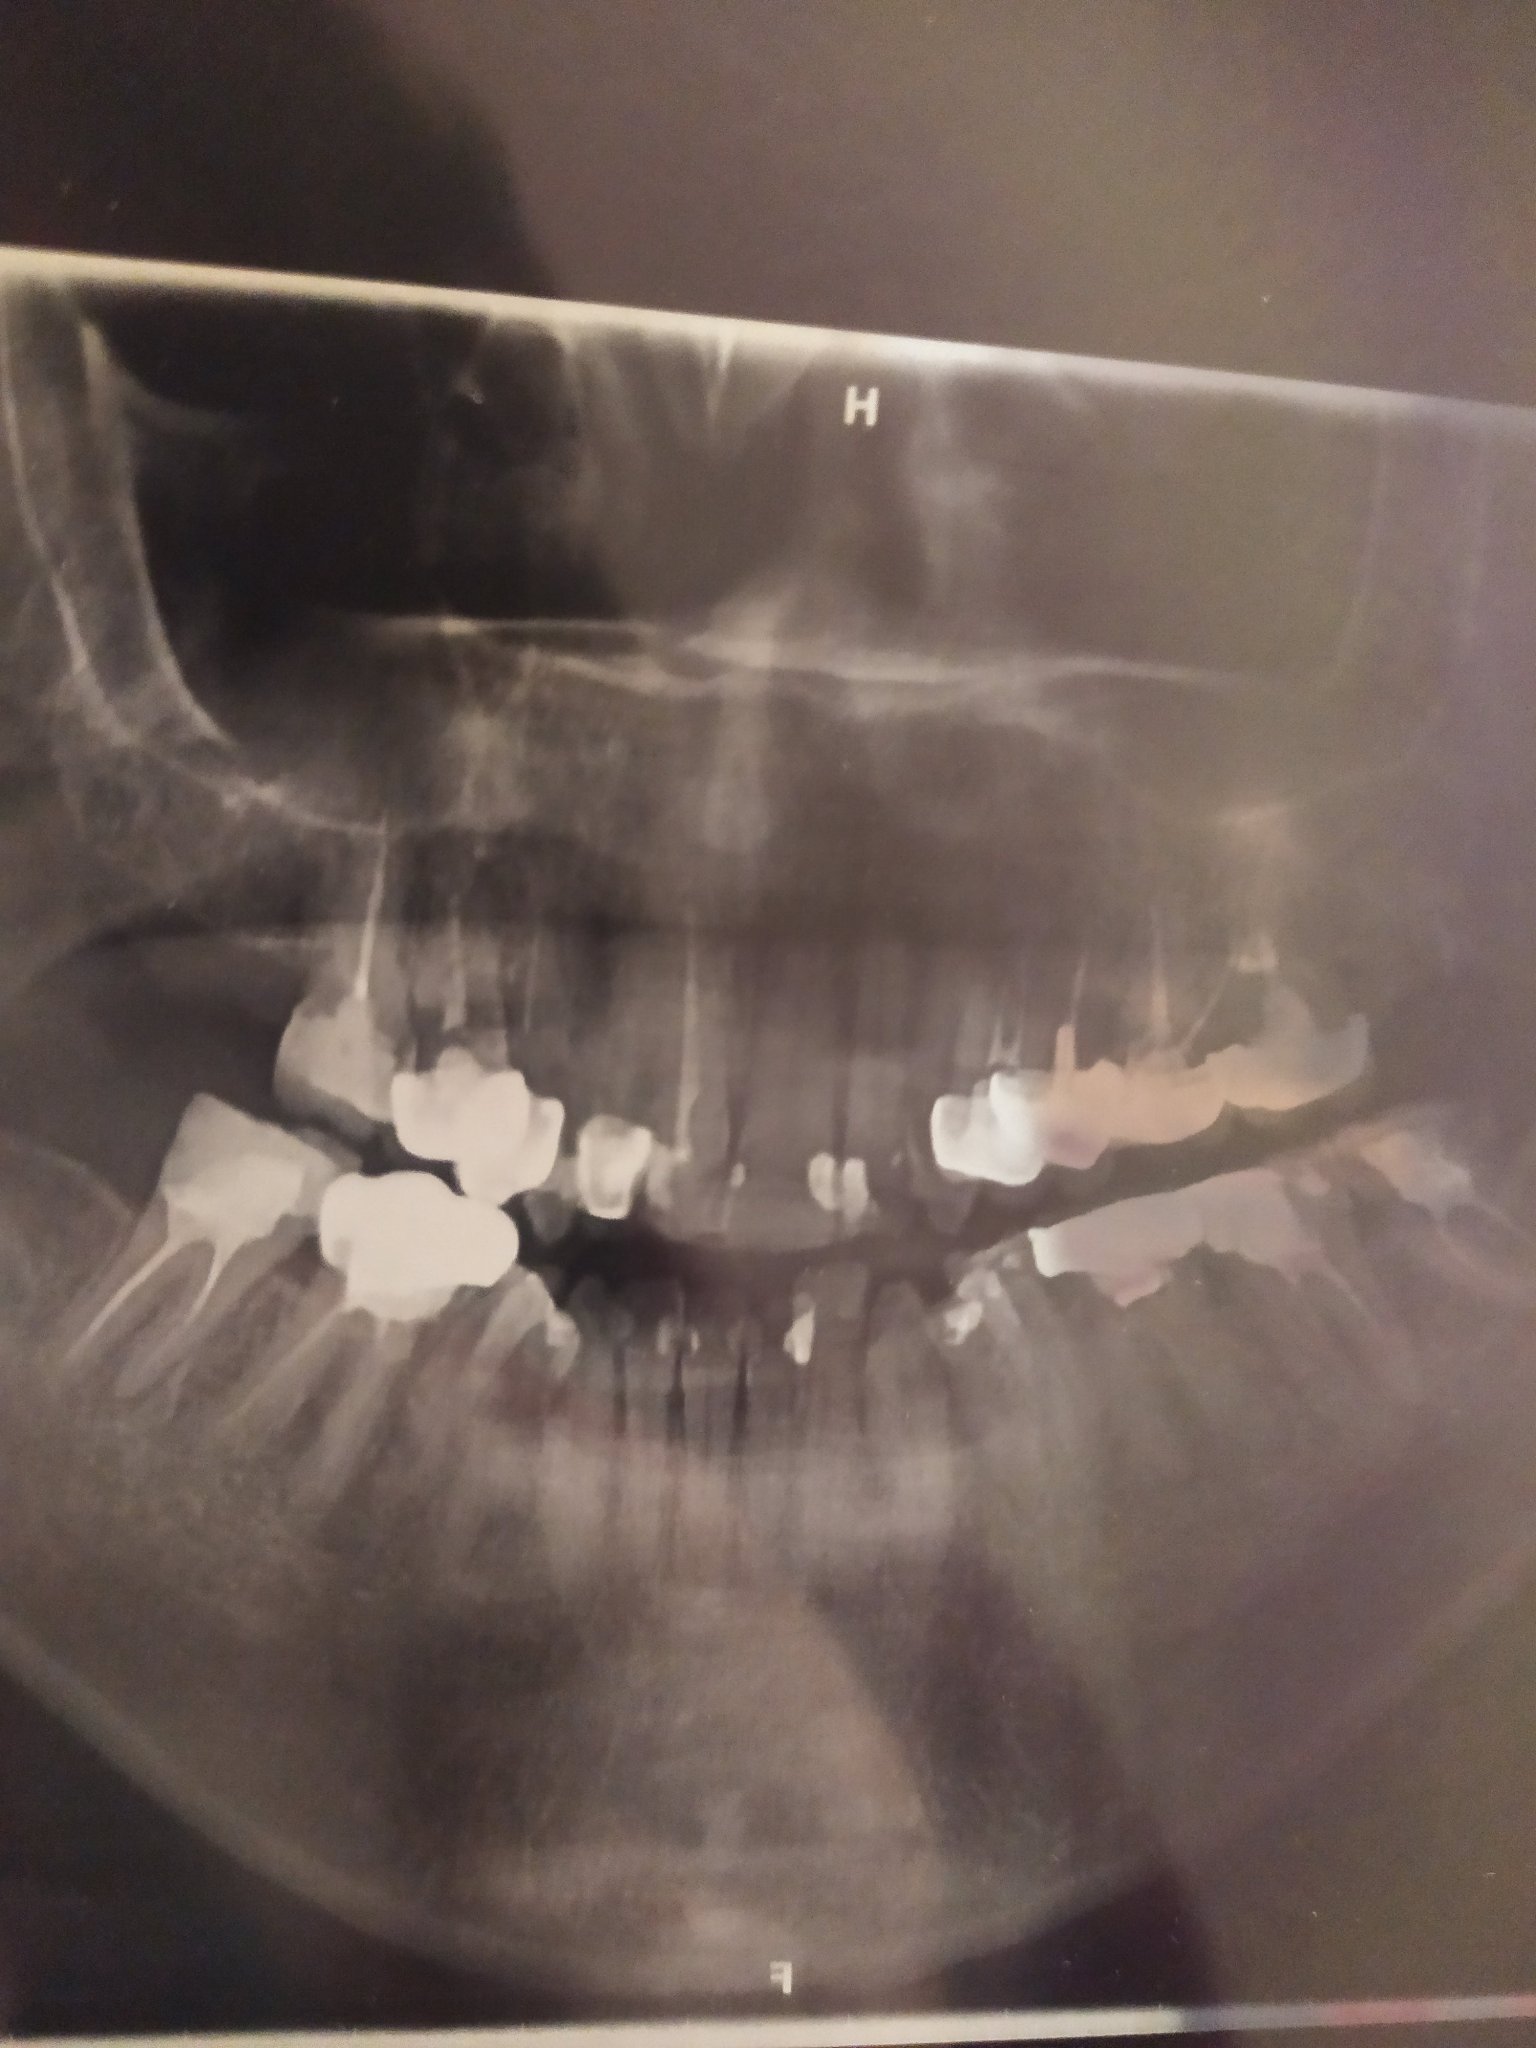

Fiffy изпратих ти лично съобщение със снимката. Още веднъж ти благодаря.

П.С. Качвам снимката и тук. Надявам се някой стоматолог да я погледне и да ми каже дали е успешно кореновото лечение и въобще каквото вижда на снимката, дали има някакви нередности.

Благодаря

Прилагам и панорамна снимка на всички зъби. Ако може някой да ми каже състоянието на зъбите и какво още има да се прави, ако има. Благодаря